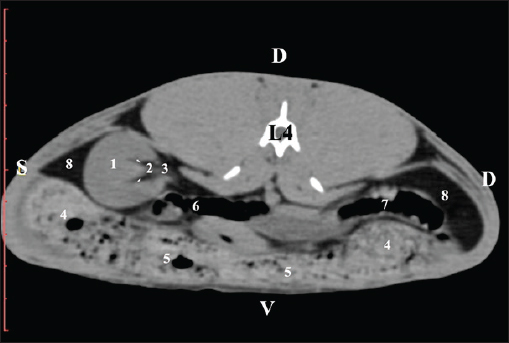

Fig. 9. Pre-contrast computed tomography (CT) anatomical scan of the regio-abdominis media at the caudal L3 edge level. (1) Ren dexter; (2) adipose collections; (3) cecum; (4) colon ascendens; (5) jejunum; (6) pars ascendens of the duodenum; (7) colon descendens. The pre-contrast anatomical scan at the L4 level provided data about the location of the renal pelvis within the renal sinus. The initial part of the pelvis renalis appeared as a distinct funnel-shaped hypoattenuated soft tissue, whose central part was widened and formed the recessus renalis. The transition of the narrowed end of the renal pelvis into the hypoattenuated left ureter was without a sharp boundary. The left kidney was in contact with the cecum, colon ascendens, and colon transversum ventrally. Crista renalis was observed as a hypoattenuated linear soft tissue finding (Figs. 10 and 11).

Fig. 10. Pre-contrast computed tomography (CT) anatomical scan of the regio-abdominis media at the cranial L4 edge level. (1) Ren sinister; (2) pelvis renalis and crista renalis; (3) ureter; (4) cecum; (5) colon ascendens; (6) colon transversum; (7) colon descendens; (8) adipose collections.

Fig. 11. Pre-contrast computed tomography (CT) anatomical scan of the regio-abdominis media at the caudal L4 edge level. (1) Ren sinister; (2) pelvis renalis; (3) ureter; (4) adipose collections; (5) cecum; (6) colon ascendens; (7) colon transversum; (8) colon descendens; (9) mesenterium; (white arrows) recessus renalis; (*) crista renalis. The L5 scan revealed the caudal end of the left kidney. It was adjacent to some small intestinal segments, including the duodenal pars ascendens, ileum, cecum, and colon ascendens (Figs. 12 and 13).